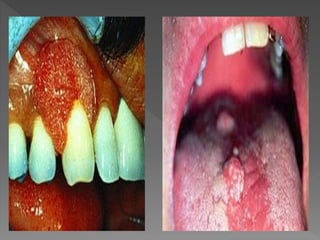

Dani apresenta HPV sintomas e prevenções

Trabalho sobre HPV